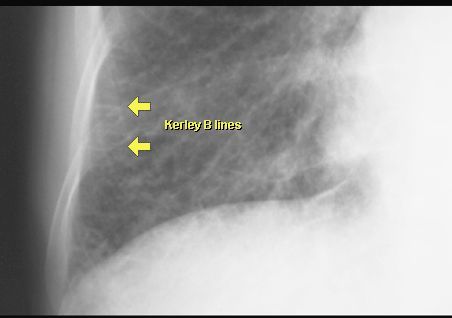

OBRZĘK PŁUC

RTG